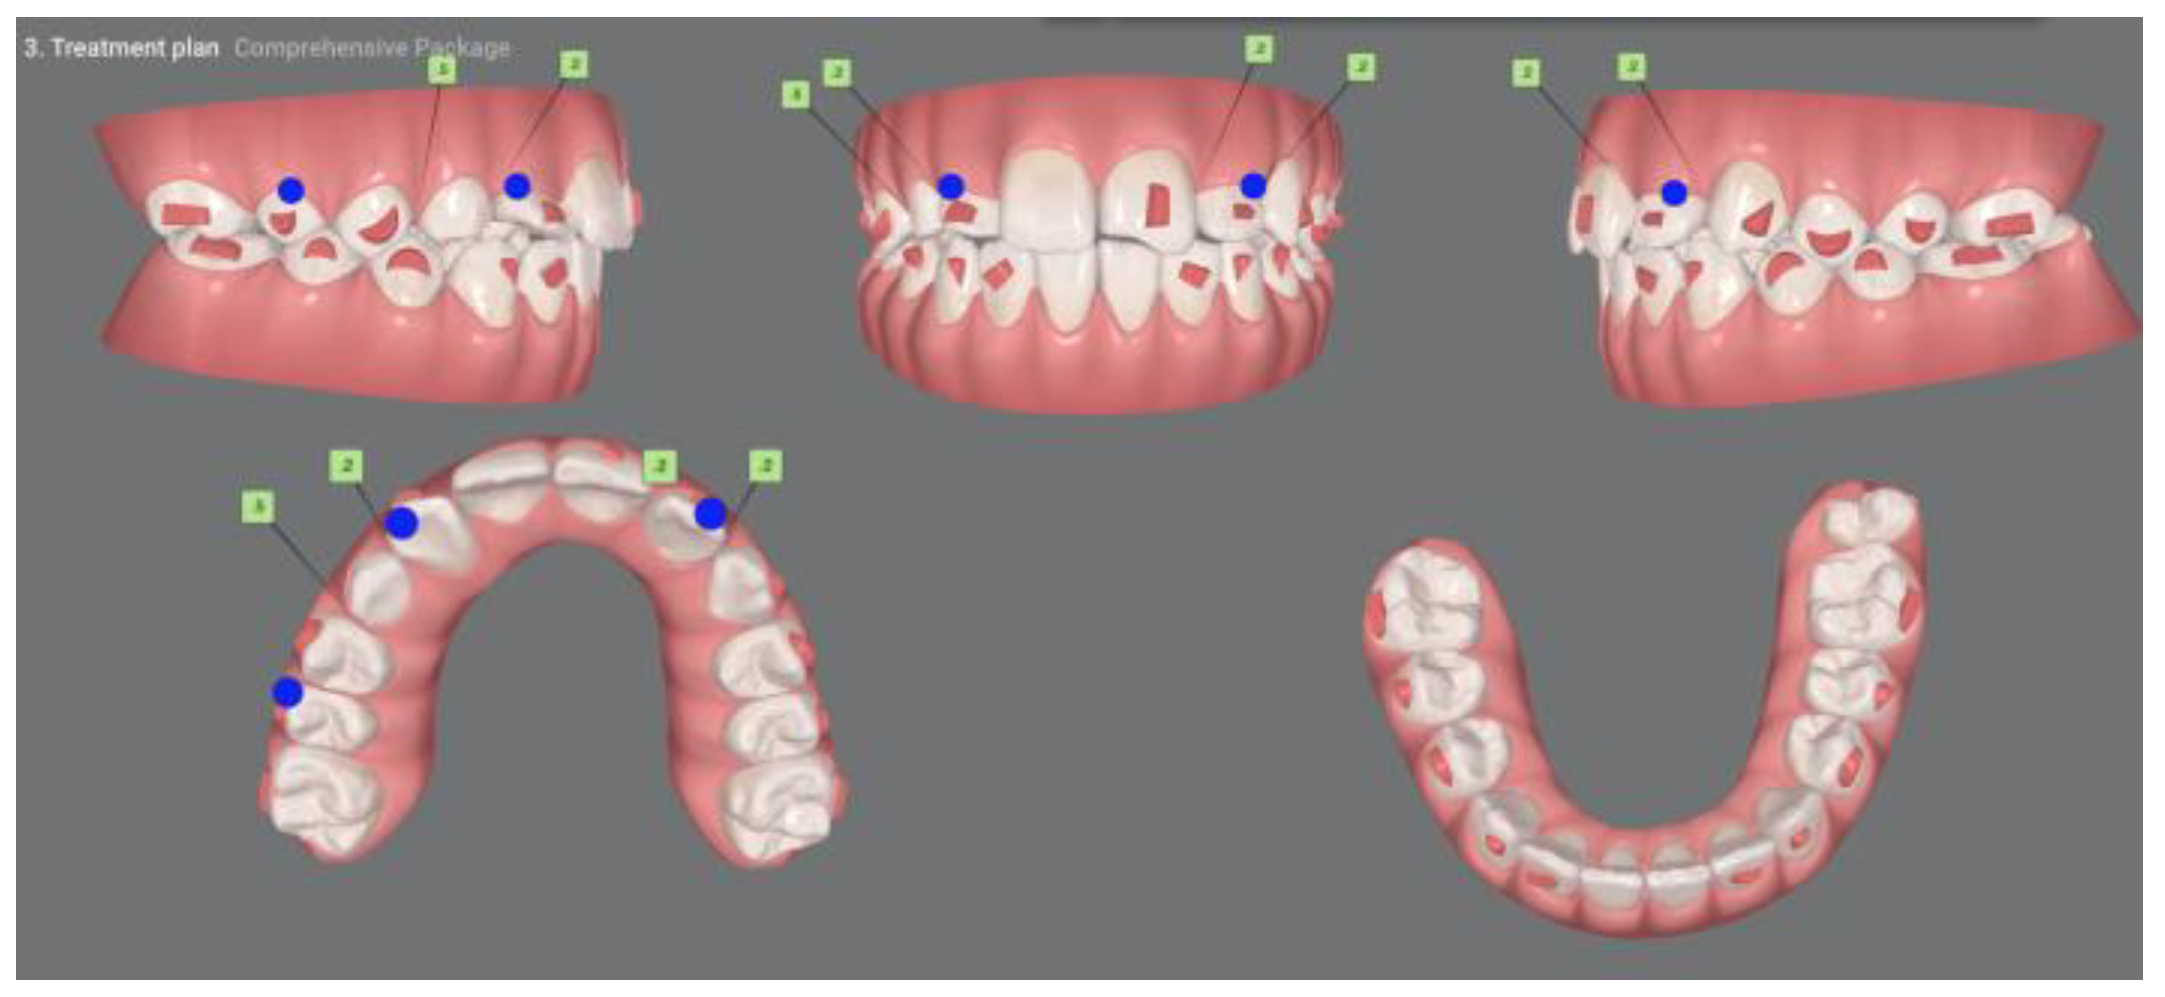

| Pinho T., Amaral R. 2025 | ♀ 13 YO | Mx.C.I1 | C | R | V (impacted) | Cl I | Maintained | -Total root resorption of tooth #11 due to the position of the ectopic canine |

3.2. Clinical Case